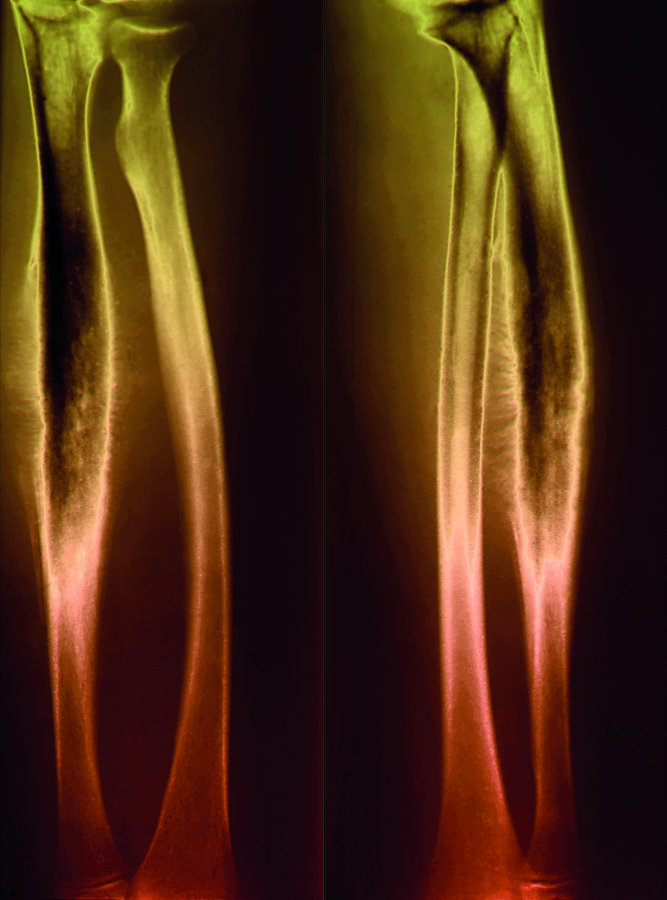

Das Ewing-Sarkom ist die zweithäufigste Form von Knochenkrebs bei Kindern. Die hochmalignen

Tumoren finden sich am häufigsten im Becken und im Oberschenkelknochen. Das Ewing-Sarkom ist die zweithäufigste Form von Knochenkrebs bei Kindern. Die hochmalignen Tumoren finden sich am häufigsten im Becken und im Oberschenkelknochen. © Science Photo Library/Zephyr